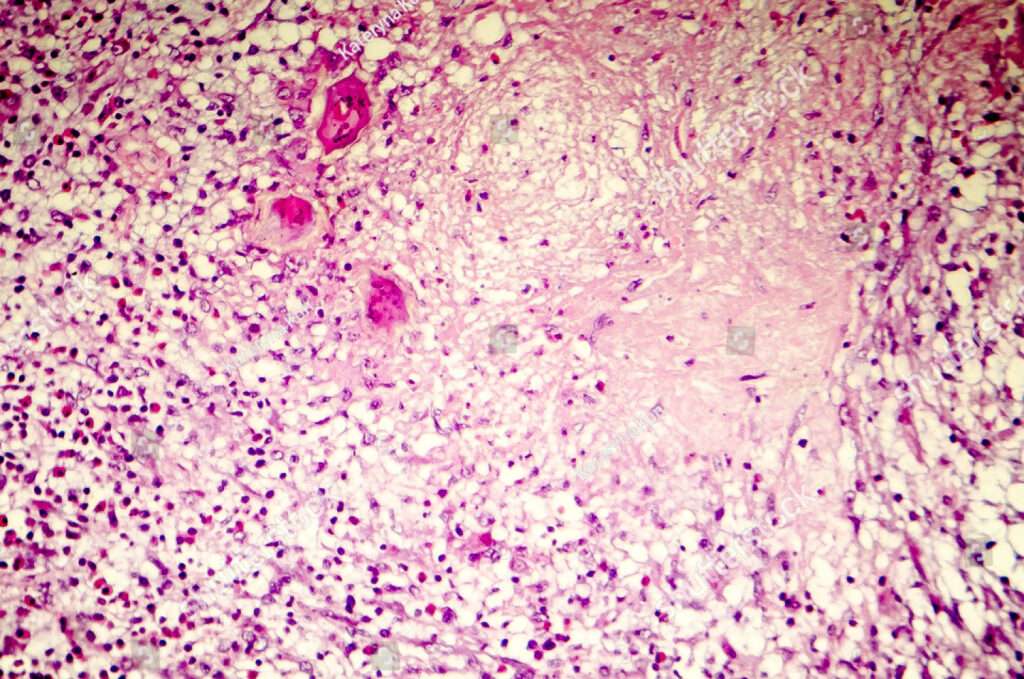

La gliosis reactiva es otra característica común de la lesión neuronal crónica. Este proceso implica la activación y proliferación de células gliales, como los astrocitos y las microglías, en respuesta al daño neuronal. La gliosis reactiva puede tener efectos tanto protectores como perjudiciales en el entorno neural, dependiendo de la naturaleza y la duración del estímulo desencadenante.

En las etapas iniciales de la enfermedad, puede ser difícil detectar la pérdida celular directamente, ya que los cambios son sutiles y pueden ser eclipsados por la respuesta glial reactiva. En muchos casos, los cambios gliales reactivos son los mejores indicadores de la lesión neuronal en curso.